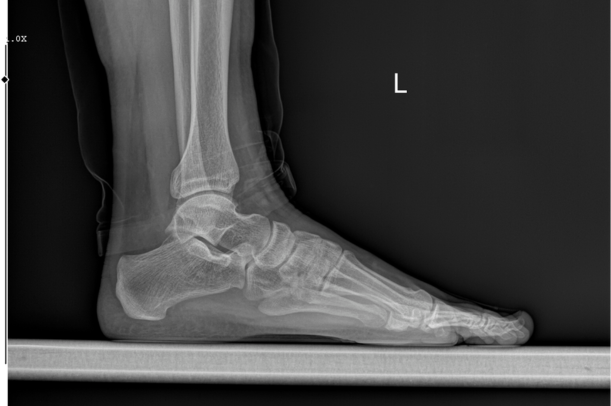

「足の親指の付け根」とは、医学的に**第一中足趾節関節(MTP関節)**と呼ばれる場所を指します。足の親指の骨と中足骨がつながる関節で、歩く・走るといった動作で体重を支える大切な部分です。この関節には「種子骨(しゅしこつ)」と呼ばれる小さな骨も存在し、地面を蹴り出すときにバネのような役割を果たしていると言われています(引用元:https://www.mediaid-online.jp/clinic_notes/information/827/)。

さらに、関節周囲には靭帯・腱・軟骨・関節包などが複雑に入り組み、動作をスムーズに行えるようになっています。親指の付け根は、人が立つ・歩く際に最も大きな力が加わる部位の一つだと考えられています。

整形外科や足専門医では、まず触診や問診で症状を確認します。そのうえで、X線検査で骨の変形や骨折を確認し、必要に応じてMRIや超音波検査で軟部組織の炎症を調べることがあるようです。痛風など代謝性疾患が疑われる場合には、血液検査で尿酸値をチェックすることも一般的だと言われています(引用元:https://www.rehasaku.net/)。